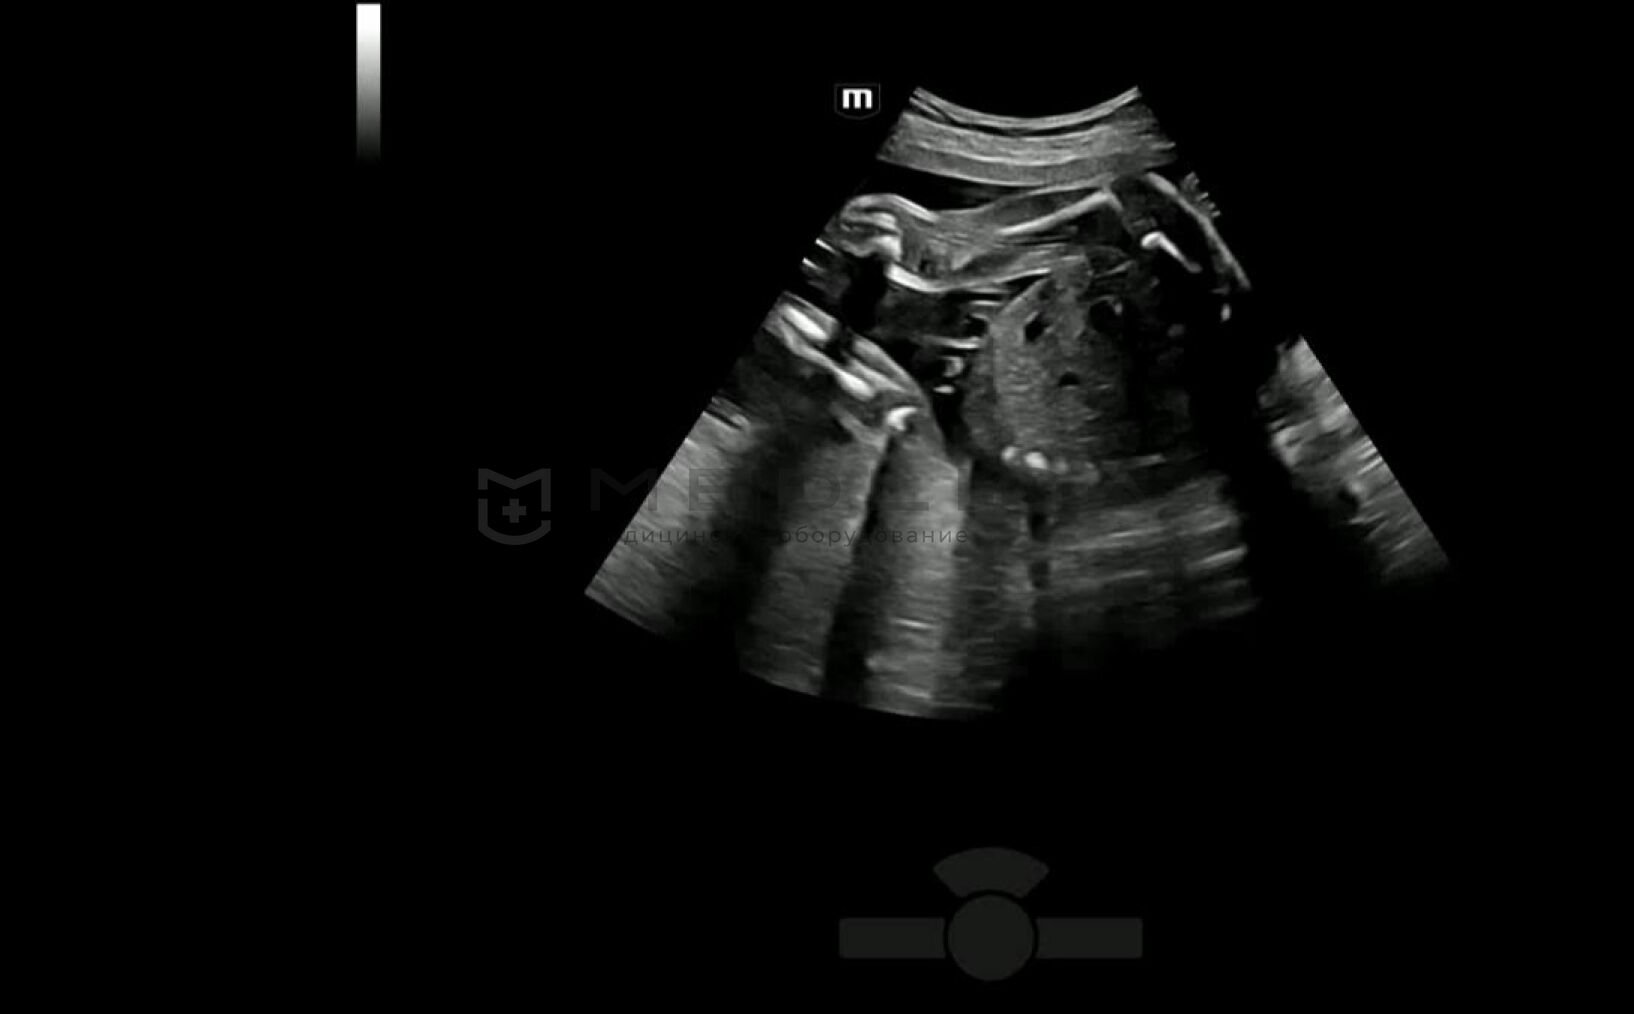

С легкостью получайте потрясающие объемные изображения лица плода.

- Автоматическое распознавание лица плода

- Автоматическая подстройка зоны интереса и положения до оптимального

- Автоматический определение параметров рендеринга лица плода

Место Smart Scene в технологии full-stack smartness